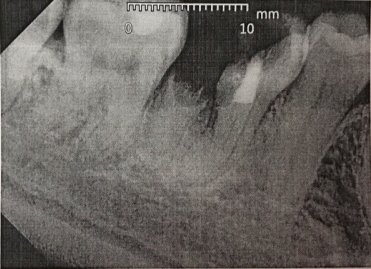

2 года назад удали нерв на верхнем зубе, со временем он стал чернеть, потом сыпаться. Сейчас от него осталась одна только маленькая часть, а внутри все черное.

Как мне быть? В данный момент нет возможности нарастить зуб, может можно пломбой закрыть?

Нет, пломбой уже такой зуб нарастить невозможно, так как для реставрации композитными материалами необходимо наличие трех стенок или 70% тканей коронковой части зуба. Если зуб можно еще восстановить, то исключительно культевой вкладкой и коронкой.